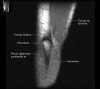

2. Axial section

1) The tendons of the Biceps Brachii and Brachiallis muscles transversely as they insert onto the Radius and Ulna respectively. 2) The distal Triceps tendon is also well evlauated in this plane.